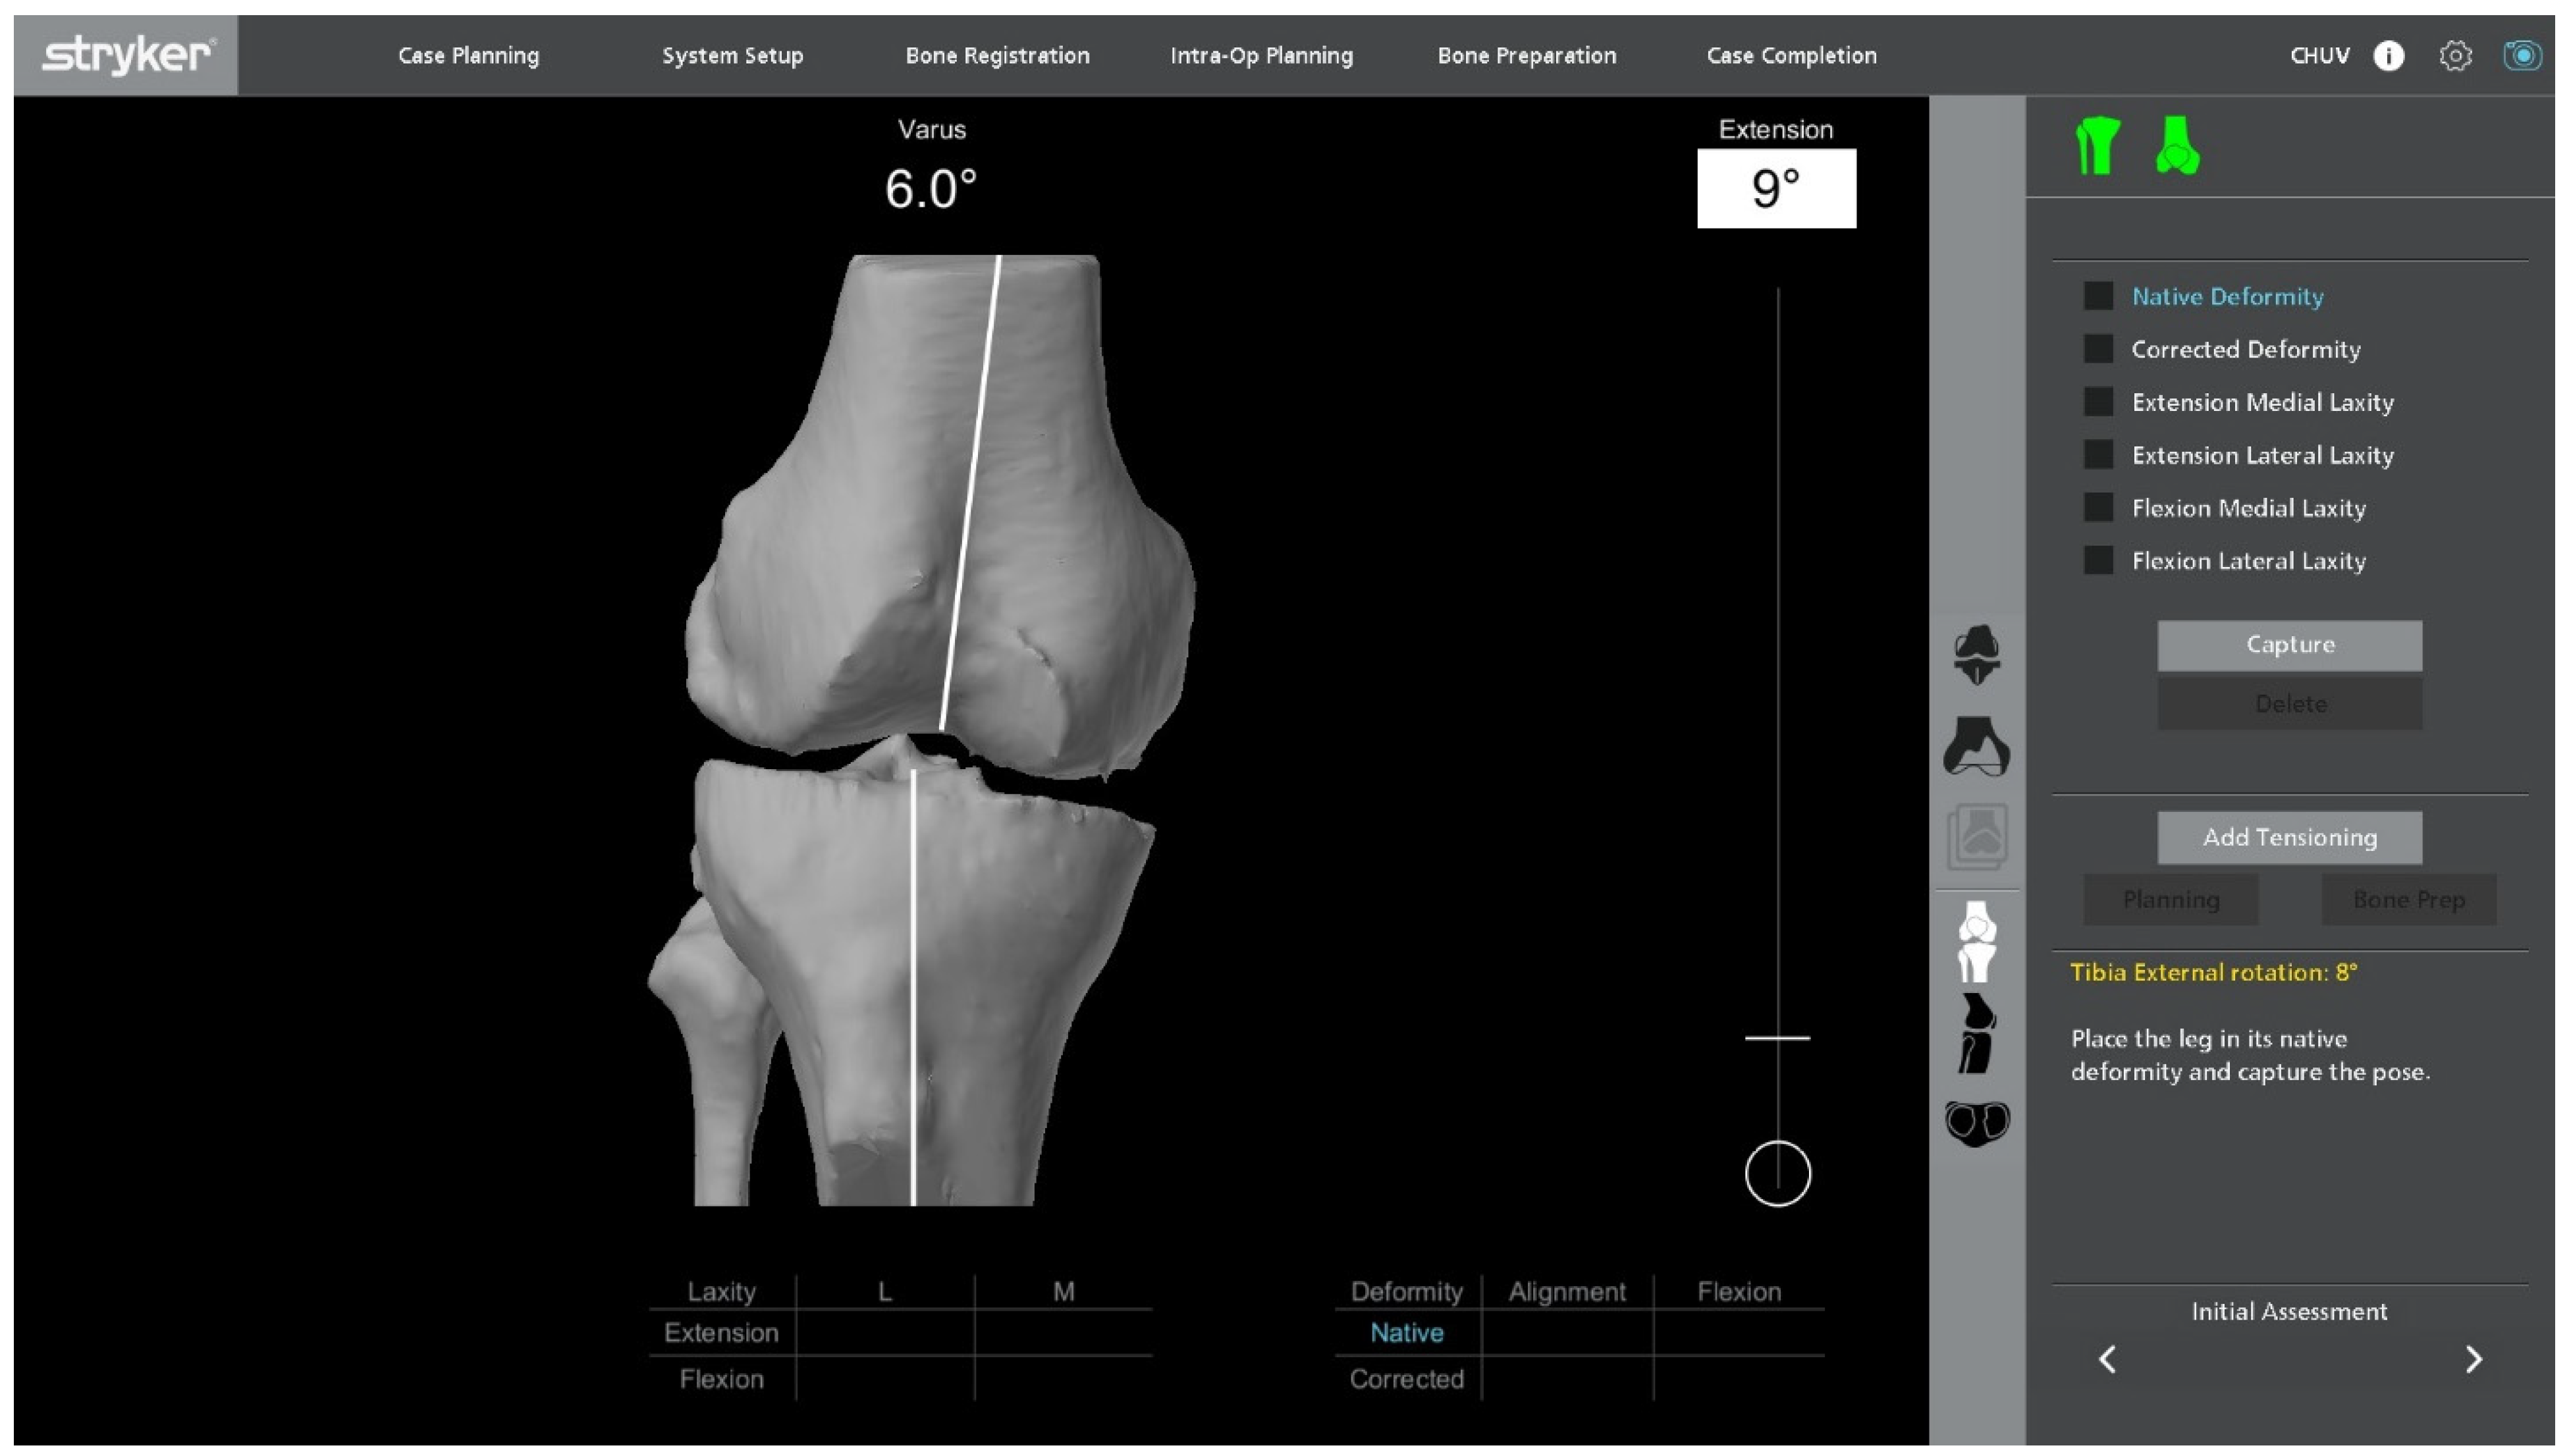

2.4. Intraoperative Functional Alignment and Ligament Balance Assessment

With the UKA components in place, an initial intraoperative functional alignment assessment is performed (Figure 3). The polyethylene insert is reinserted to enable a dynamic evaluation of ligament balance in both flexion and extension, providing essential data for potential plan adjustments. After registration and verification of reference points, this assessment is repeated through the full range of motion, allowing real-time adaptation to refine the 3D plan.

Figure 3.

Intraoperative ligament balance assessment after registration. The polyethylene insert is reinserted prior to implant removal to evaluate dynamic ligament balancing through flexion and extension.

Varus–valgus stress tests are applied at multiple flexion angles to assess ligament balance. The target is 1–2 mm of controlled laxity with symmetric medial and lateral gaps in extension and at 90° of flexion. The medial–lateral side-to-side difference should be ≤1 mm to maintain optimal soft-tissue tension and avoid mid-flexion instability.

Within a functional-alignment strategy, balance is restored by adjusting implant positioning and resection targets rather than by performing ligament or soft-tissue releases. This bone-preserving functional-alignment strategy maintains the native joint line and creates optimal conditions for accurate, conservative implantation.